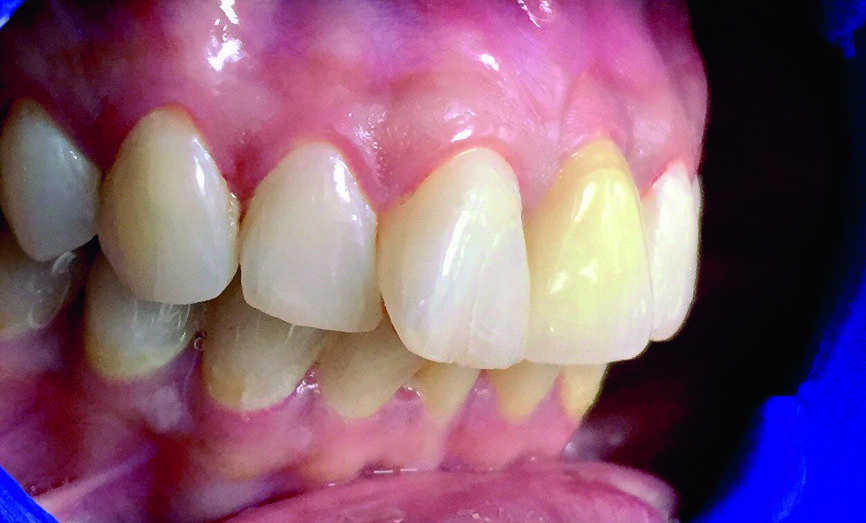

La patiente, âgée de 36 ans, nous a consulté pour un contrôle dentaire en raison d’une douleur dans la région des dents antérieures supérieures gauches. À ses dires, la douleur commençait subitement et s’aggravait lors de la mastication. L’examen clinique de l’incisive centrale supérieure gauche (dent 21) a révélé une inflammation, une douleur à la percussion et une fracture de la dent au niveau de la limite cervicale. La dent avait fait l’objet d’un traitement endodontique trois ans plus tôt et n’avait jamais été restaurée auparavant. Une radiographie a montré une couronne fracturée touchée par une résorption radiculaire mineure ainsi qu’une infection périapicale (Figs. 1a–c). L’examen radiographique comme l’examen clinique ont également confirmé la présence d’une largeur et d’une hauteur d’os suffisantes. Le pronostic très défavorable d’un retraitement endodontique a été expliqué à la patiente et elle a opté pour un traitement plus radical. La décision d’extraire la dent et de la remplacer immédiatement par un implant monobloc en zircone a donc été prise.

Fig. 1a : Photographie clinique préopératoire de la dent 21.